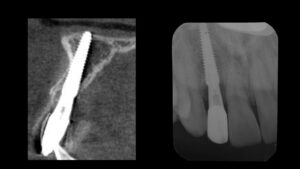

レントゲン写真でも、適切な位置と方向で埋入できたことがわかります。

セラミックのセット後のレントゲン写真でも良好な適合状態が確認できます。